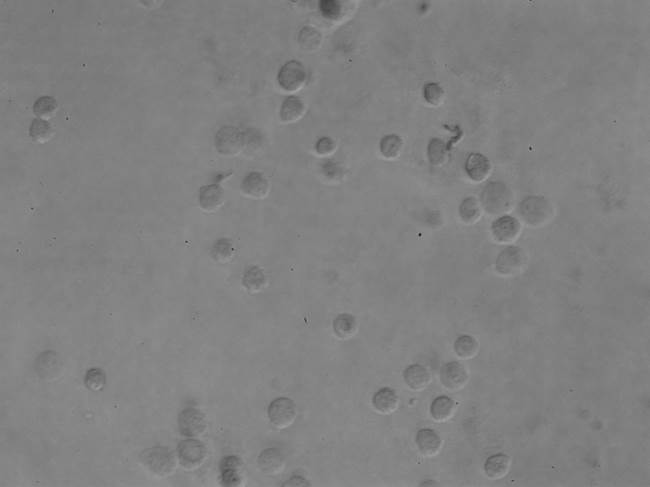

30 March 2015 Phase contrast microscopy ( living brain cancer cell ) Phase contrast microscopy living brain cancer cell Prev Next